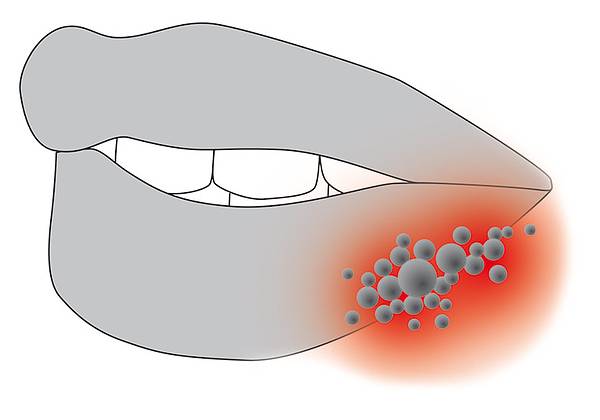

- Lippenherpes

Mit dieser Methode können Bakterien sehr effektiv und ohne Schmerzen und Nebenwirkungen abgetötet werden. Das angewandte Licht wirkt wie ein Antibiotikum (Cumdente).

- Lippenherpes

© Cumdente